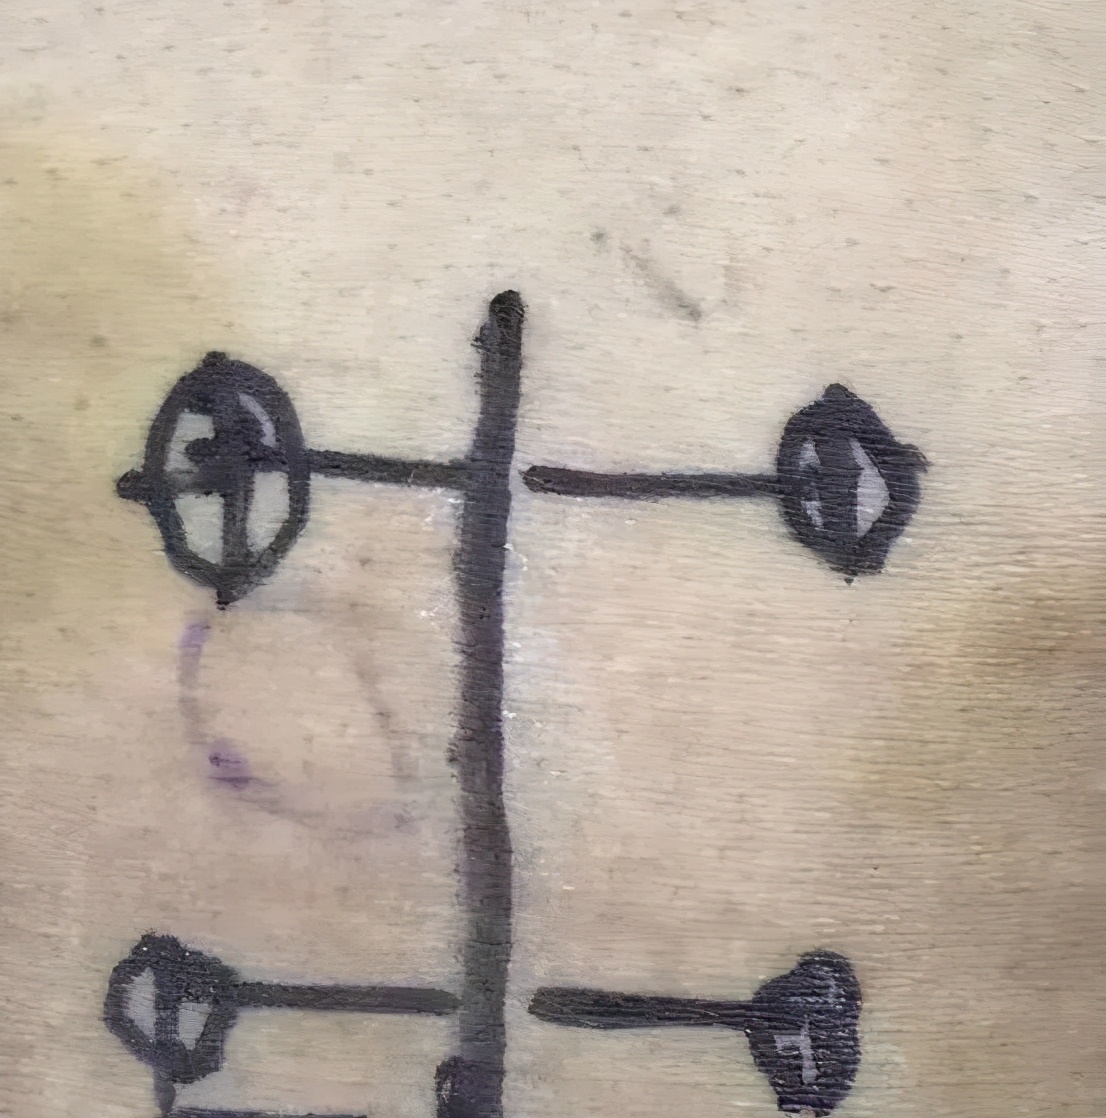

- 术中 -

- 术中 -

术中只需在患者背部切两处约1cm长的小切口,在关节镜辅助下,清晰显露神经根及突出椎间盘,操作空间自由灵活,手术难度小,过程轻松、顺利。